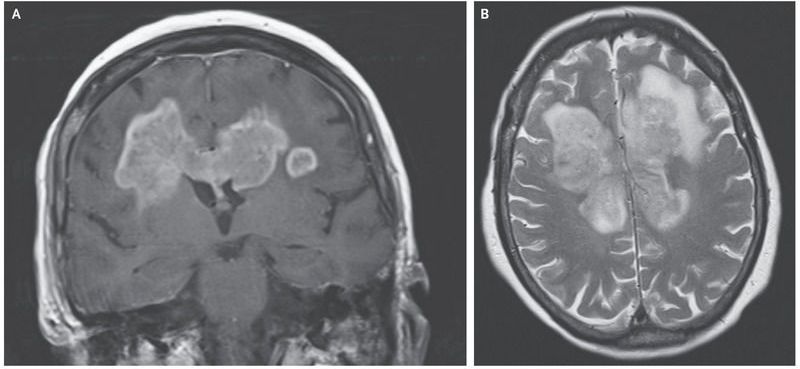

An 83-year-old woman presented to the emergency department with a 5-hour history of weakness in the left arm, drooping on the right side of the face, slurred speech, and urinary incontinence. A 7-week history of progressive functional and cognitive decline was reported. Gadolinium-enhanced magnetic resonance imaging (MRI) of the head showed a solid, enhancing lesion on the T1-weighted sequence, with a butterfly appearance that extended across the corpus callosum (Panel A). Hyperintensity of the mass was observed on the T2-weighted sequence (Panel B), and restricted diffusion was seen on diffusion-weighted MRI. The differential diagnosis for lesions that extend across the corpus callosum and symmetrically into the frontal lobes includes glioblastoma and primary central nervous system lymphoma. A biopsy of the right frontal lobe revealed a glioblastoma. After discussion regarding the limited treatment options, including radiation and chemotherapy, for this extensive tumor, the patient and family opted for supportive, palliative management. The patient died 3 weeks later.